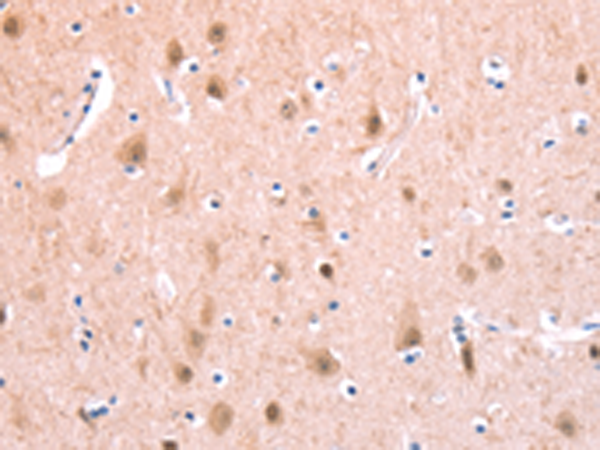

分类: 科研抗体货号: P07698别名: CMM8; OCA1A; OCAIA; SHEP3应用: WB,IHC反应种属: Human, Mouse